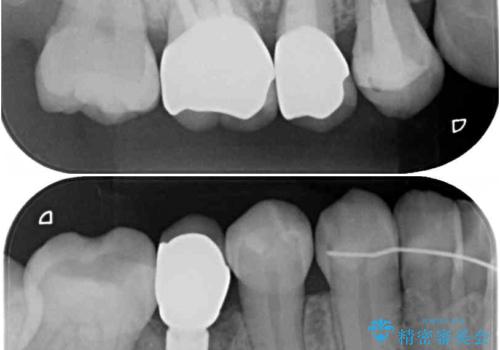

前歯のクロスバイトはインビザラインで改善し、抜歯が必要な部分はインプラントを、その他むし歯が進行している歯はセラミッククラウンによる補綴治療することとしました。

仕事がお忙しく、インビザラインをあまりしっかりと使用できなかったようで、何とか長い期間をかけて歯列を整えることができました。

磨きにくく、何度もむし歯治療を繰り返していた前歯をスッキリと整えることができました。